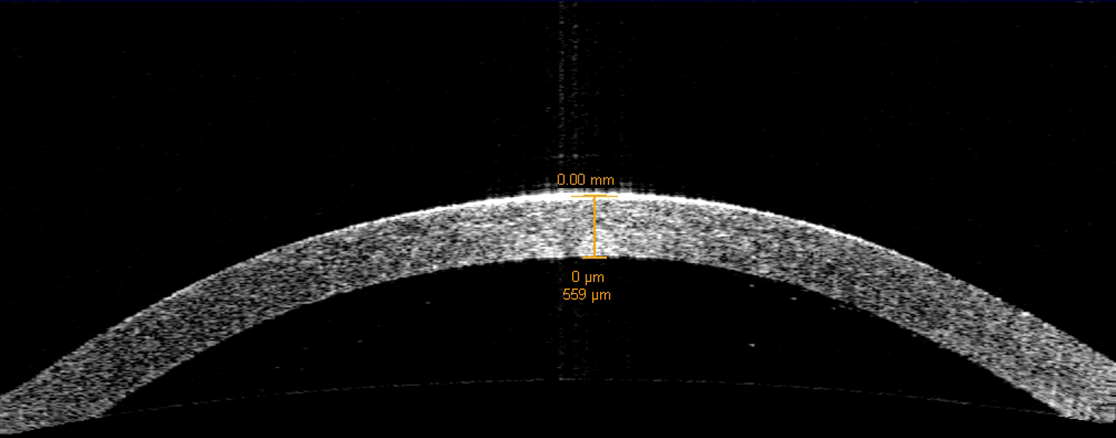

A typical cornea before processing for DSAEK. OCT examination shows the cornea is 569 microns thick.

OCT images accompany every EK tissue processed by RMLEB.